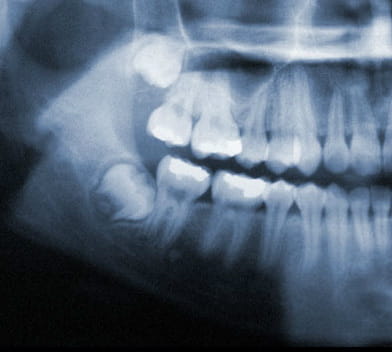

X-Ray of wisdom teeth

Wisdom teeth under ideal circumstances should grow in straight like any other tooth. However, it is common for wisdom teeth to become impacted inside the jaw or just under the gums. If this occurs, your wisdom teeth should be removed.

Common Impactions:

1. Horizontal Impaction

2. Angular Impaction

3. Vertical Impaction

4. Soft Tissue Impaction